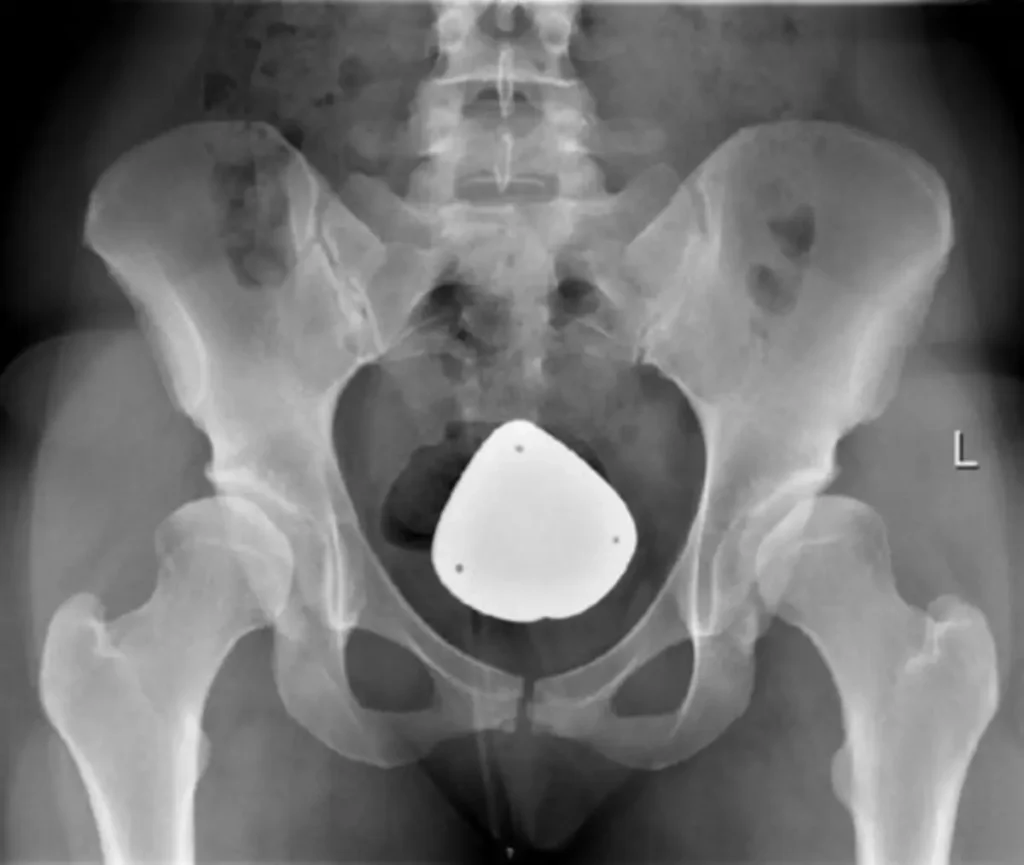

Schwere Fälle: In schwereren Fällen kann eine Operation erforderlich sein. Diese Operation wird in der Regel erst durchgeführt, wenn das Kind älter ist.